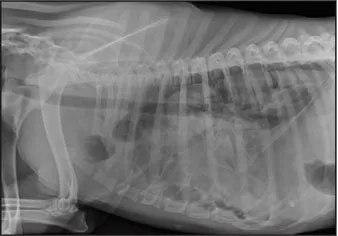

CASE 1.1 A 7-year-old neutered male Labrador Retriever who was hit by a car. You obtain these thoracic radiographs: Figs. 1.1a, b, left and right lateral projections, respectively; Figs. 1.1c, d, ventrodorsal and dorsoventral projections, respectively.

1 What are your radiographic findings?

2 What is your radiographic diagnosis?

1.1a

1.1b

1.1c

1.1d